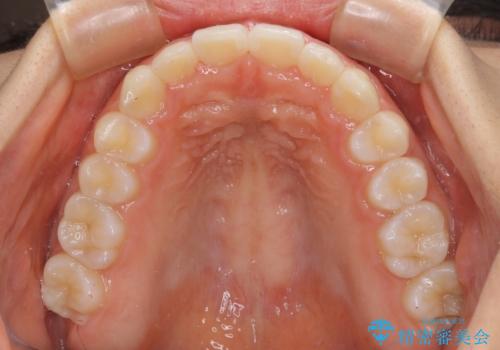

前歯のデコボコと突出感 インビザラインによる矯正治療

- 上下前歯のデコボコと、上顎前歯の突出感を気にして来院された患者様です。

インビザラインによる上下歯列の側方拡大と後方移動、IPR(歯と歯の間を削る)にるスペースの獲得により歯列を整えることとしました。

毎日22時間以上しっかりとマウスピースを装着していただいたので、スムーズに治療が進みました。歯と歯の間を削ることでうまくスペースコントロールでき、1年強で終えることができました。